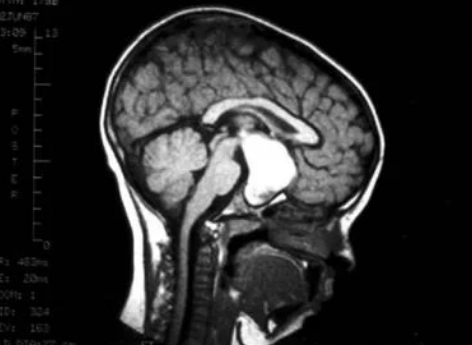

小金(化名)6岁时,开始间断性的出现无力、厌食情况,跟小朋友们一起玩的时候也无精打采。家长以为是孩子有情绪,或是挑食习惯所致,就没当回事。随着时间过去,小金的无力症状加重,恶心呕吐、进食不佳、状态低迷,出现嗜睡、左眼无光感等症状,到医院经过头部CT检查后才发现,小金患上了小儿颅咽管瘤。

小儿颅咽管瘤是一种少见的中枢神经系统(CNS)良性肿瘤,被认为是由Rathke氏囊的残余物引起的,靠近垂体。颅咽管瘤在儿童中常见,占儿童鞍区肿瘤的54%,鞍上区是大脑中蝶鞍上方的区域,而蝶鞍是脑下垂体所在的头骨部分。所以,随着肿瘤的扩大,正常的垂体组织会被压缩并受损,导致部分或全部垂体激素的分泌逐渐丧失。这一肿瘤往往会导致失明、生长发育迟滞、甚至死亡的后果,常被人称为“长在恶性区域的良性瘤”。